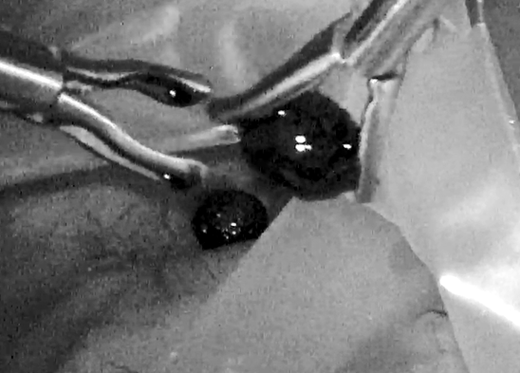

11月26日,肖广发教授团队利用3D腹腔镜联合胆道镜实施保胆取石术,手术共取出2颗直径约1cm的结石及细小泥沙样结石,经胆道镜确认,胆囊内无残留结石。术后,仅在患者腹部留下4个0.5cm-1cm的小孔,术后6小时,患者便可下床走动。